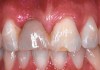

Fig 10. The provisional after 6 months of healing.

Figure 10

Fig 12. Provisionalization allows complete development of the soft tissue, evaluation of the incisal length, and final patient approval before moving to a final restoration.

Figure 12